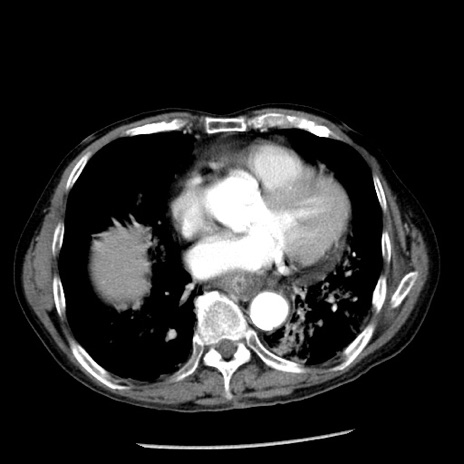

症例26(横断像)

冠状断像

【症例】80歳代男性

【主訴】嘔吐

【現病歴】昨晩2回嘔吐あり、今朝になっても嘔吐あり。来院。

【既往歴】胃潰瘍

【身体所見】意識清明、BT 37.6℃、BP 166/95mmHg、HR 100bpm、SpO2 97%、腹部:平坦・軟、腸蠕動音聴取良好、圧痛なし。

【データ】WBC 21900、CRP 1.46